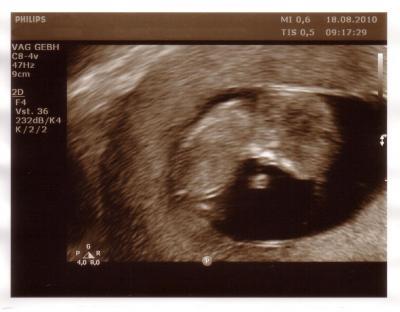

Hi Ihr! Bin zurück vom FA und bei uns ist auch alles super. Würmchen hat mir fröhlich zugewunken. Nach der Größe hab ich vergessen zu fragen, aber die Ärztin meinte, dass alles gut gewachsen ist. Außerdem hab ich meinen Mutterpass und ein neues Foto bekommen. Ich bin so überglücklich. Bin ja gerade in der 11. Woche und damals bei meiner FG hab ich die schlechten Neuigkeiten in der 11. Woche bekommen. Bei der Schwangerschaft mit meiner Tochter und auch jetzt war das deswegen irgendwie die Angstwoche. Geschafft. Jetzt noch eine gute Woche durchhalten und dann dürfen es alle wissen. LG

Sehr süßes Bildchen

Ein Süßes Bild. Echt toll. Alles Gute für dich. GlG Claudia

Genau,... richtig süsses Bild! Das Menschlein kuschelt sich so schön an! Ganz entspannt! Schön das alles o.k. ist. Ich drücke auch weiter die Daumen. LG, Manu.

Hui, das ist wirklich ein super Bild vom Krümel!

Die Größe weiß ich übrigens doch, steht nämlich im Mutterpass.

4,3 cm.